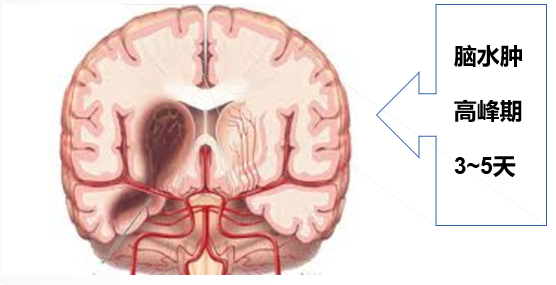

1.清除自由基、脑保护治疗,必要时候减轻脑水肿治疗,